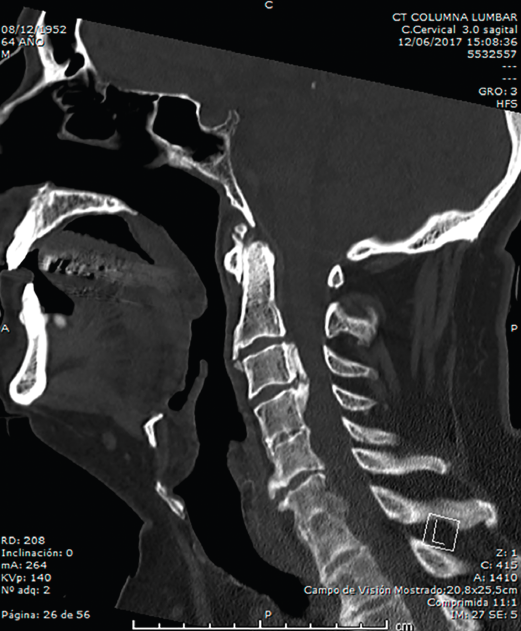

En la Figura 3 puede verse un corte sagital de la TAC cervical con sindesmofitosis también a este nivel, provocando un verdadero canal estrecho cervical en el raquis cervical alto.

Figura 3. Corte sagital de tomografía axial computarizada cervical.